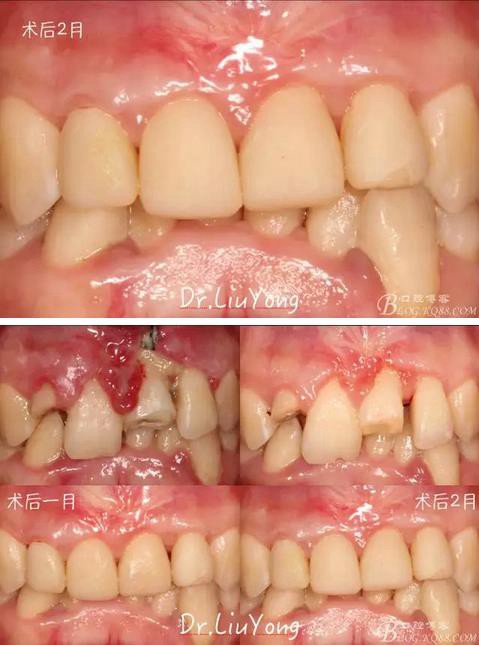

臨時(shí)修復(fù)體戴入后1月,復(fù)查,唇側(cè)觀如上圖

膜齦手術(shù)后2月復(fù)查,可以明顯觀察到,B12之間的牙齦乳頭明顯高度增加,黑三角得到很大改善,如下圖:

最終A2-B2全瓷修復(fù)體戴入口內(nèi),如下圖:

術(shù)前到最終修復(fù)歷時(shí)半年余,如下圖: